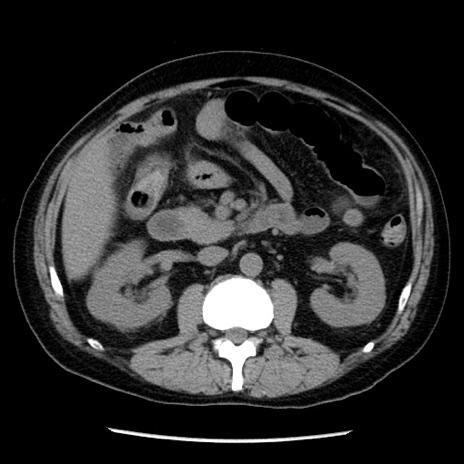

症例29(横断像)

【症例】40歳代男性

【現病歴】2日前から胃痛あり。徐々に周期的な激痛に変化した。本日になっても激痛があるため受診。

【身体所見】意識清明、BT 38-39℃台あり、腹部:膨満、やや硬、右下腹部に圧痛あり。

【データ】WBC 8500、CRP 23.26